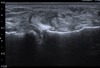

Diagnosis?

Partial Ulnar Collateral Ligament Tear

- Throbwers, anterior bundle of ulnar collateral ligament torn (medial and poster bundles can also be involved)

- T sign